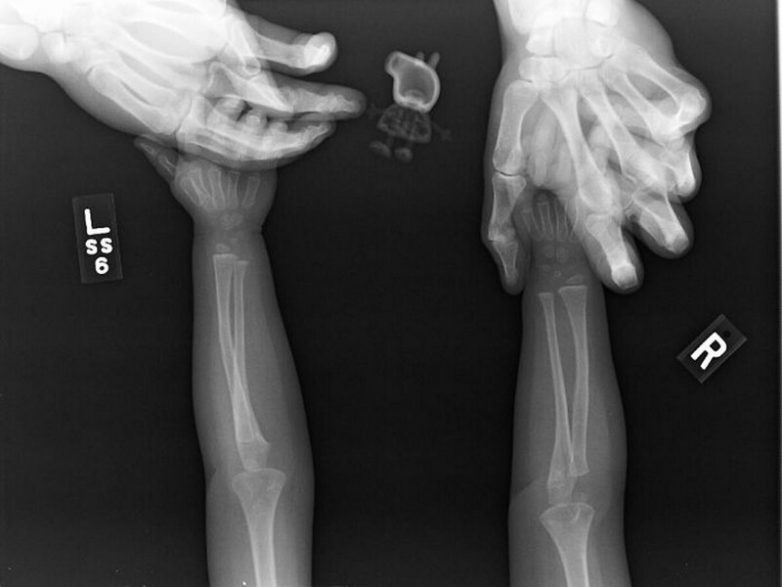

Маленькая девочка попросила врача, чтобы свинке Пеппе сделали рентген вместе с ней